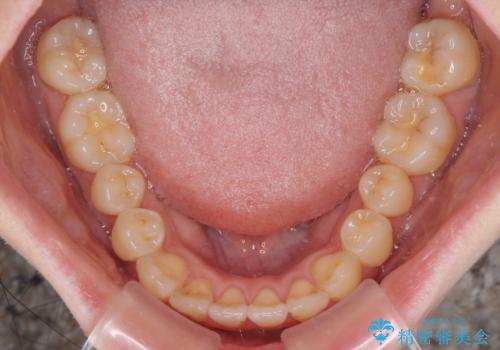

気になるデコボコとオープンバイト インビザラインでの矯正治療

- 前歯のデコボコと上下が開いていることを気にして来院された患者様です。

いわゆるオープンバイトは、インビザラインによる治療が適しているため、インビザラインにて治療を行うこととしました。

オープンバイトは容易に後戻りを起こすため、少しでも後戻りリスクを軽減するために舌癖改善のトレーニングをしっかりと行っていただきました。